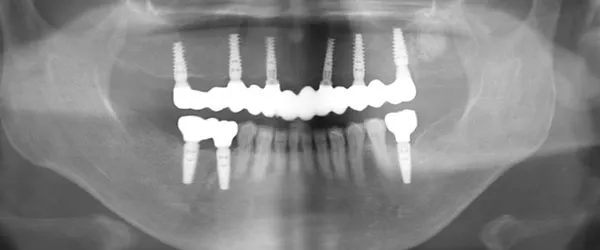

39歳 / 女性

上の前歯2番目と3番目の左右が乳歯のままで大人の歯が生えてこない。これから どうしたら良いのか相談したい。

治療内容

ガイディッドサージェリーにてインプラントを埋入。上の前歯に4本埋入。

治療期間

インプラントが骨につくまで4か月。治療終了までに約1年。